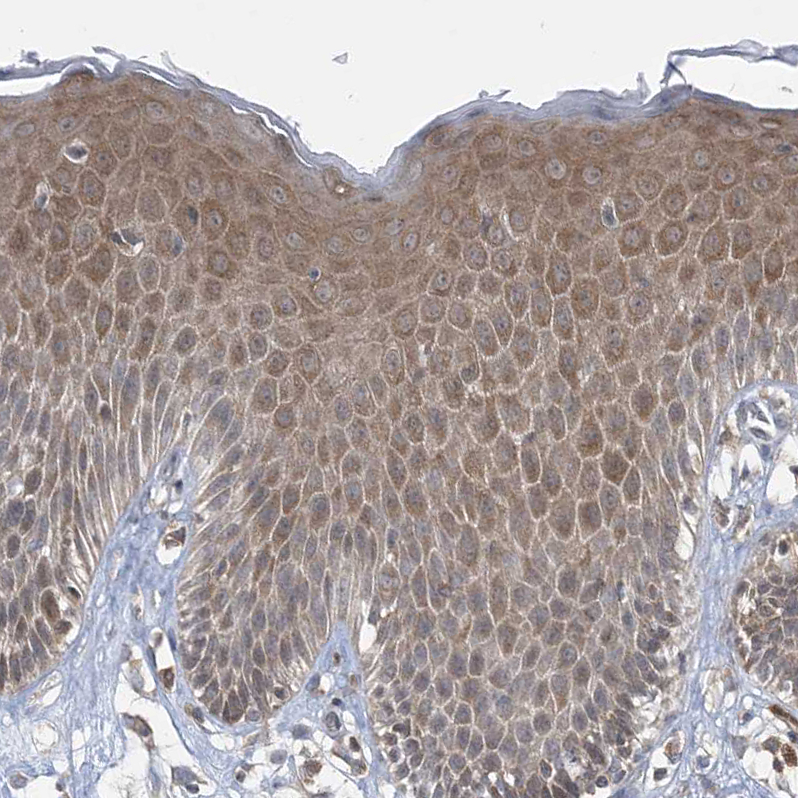

Immunohistochemical staining of human Lymph node shows strong membranous and cytoplasmic positivity in non-germinal center cells.